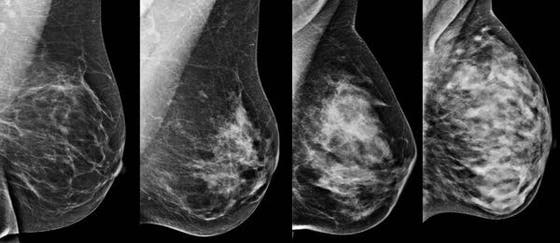

The DENSE trial investigated whether it makes sense to add an MRI to the breast cancer population screening for women with very dense breast gland tissue. The results of this ten-year study show that an MRI in these women is much better able than a mammogram to detect breast cancer at an early stage. Because the tumors are found earlier, they are on average smaller and less often spread, and therefore easier to treat.